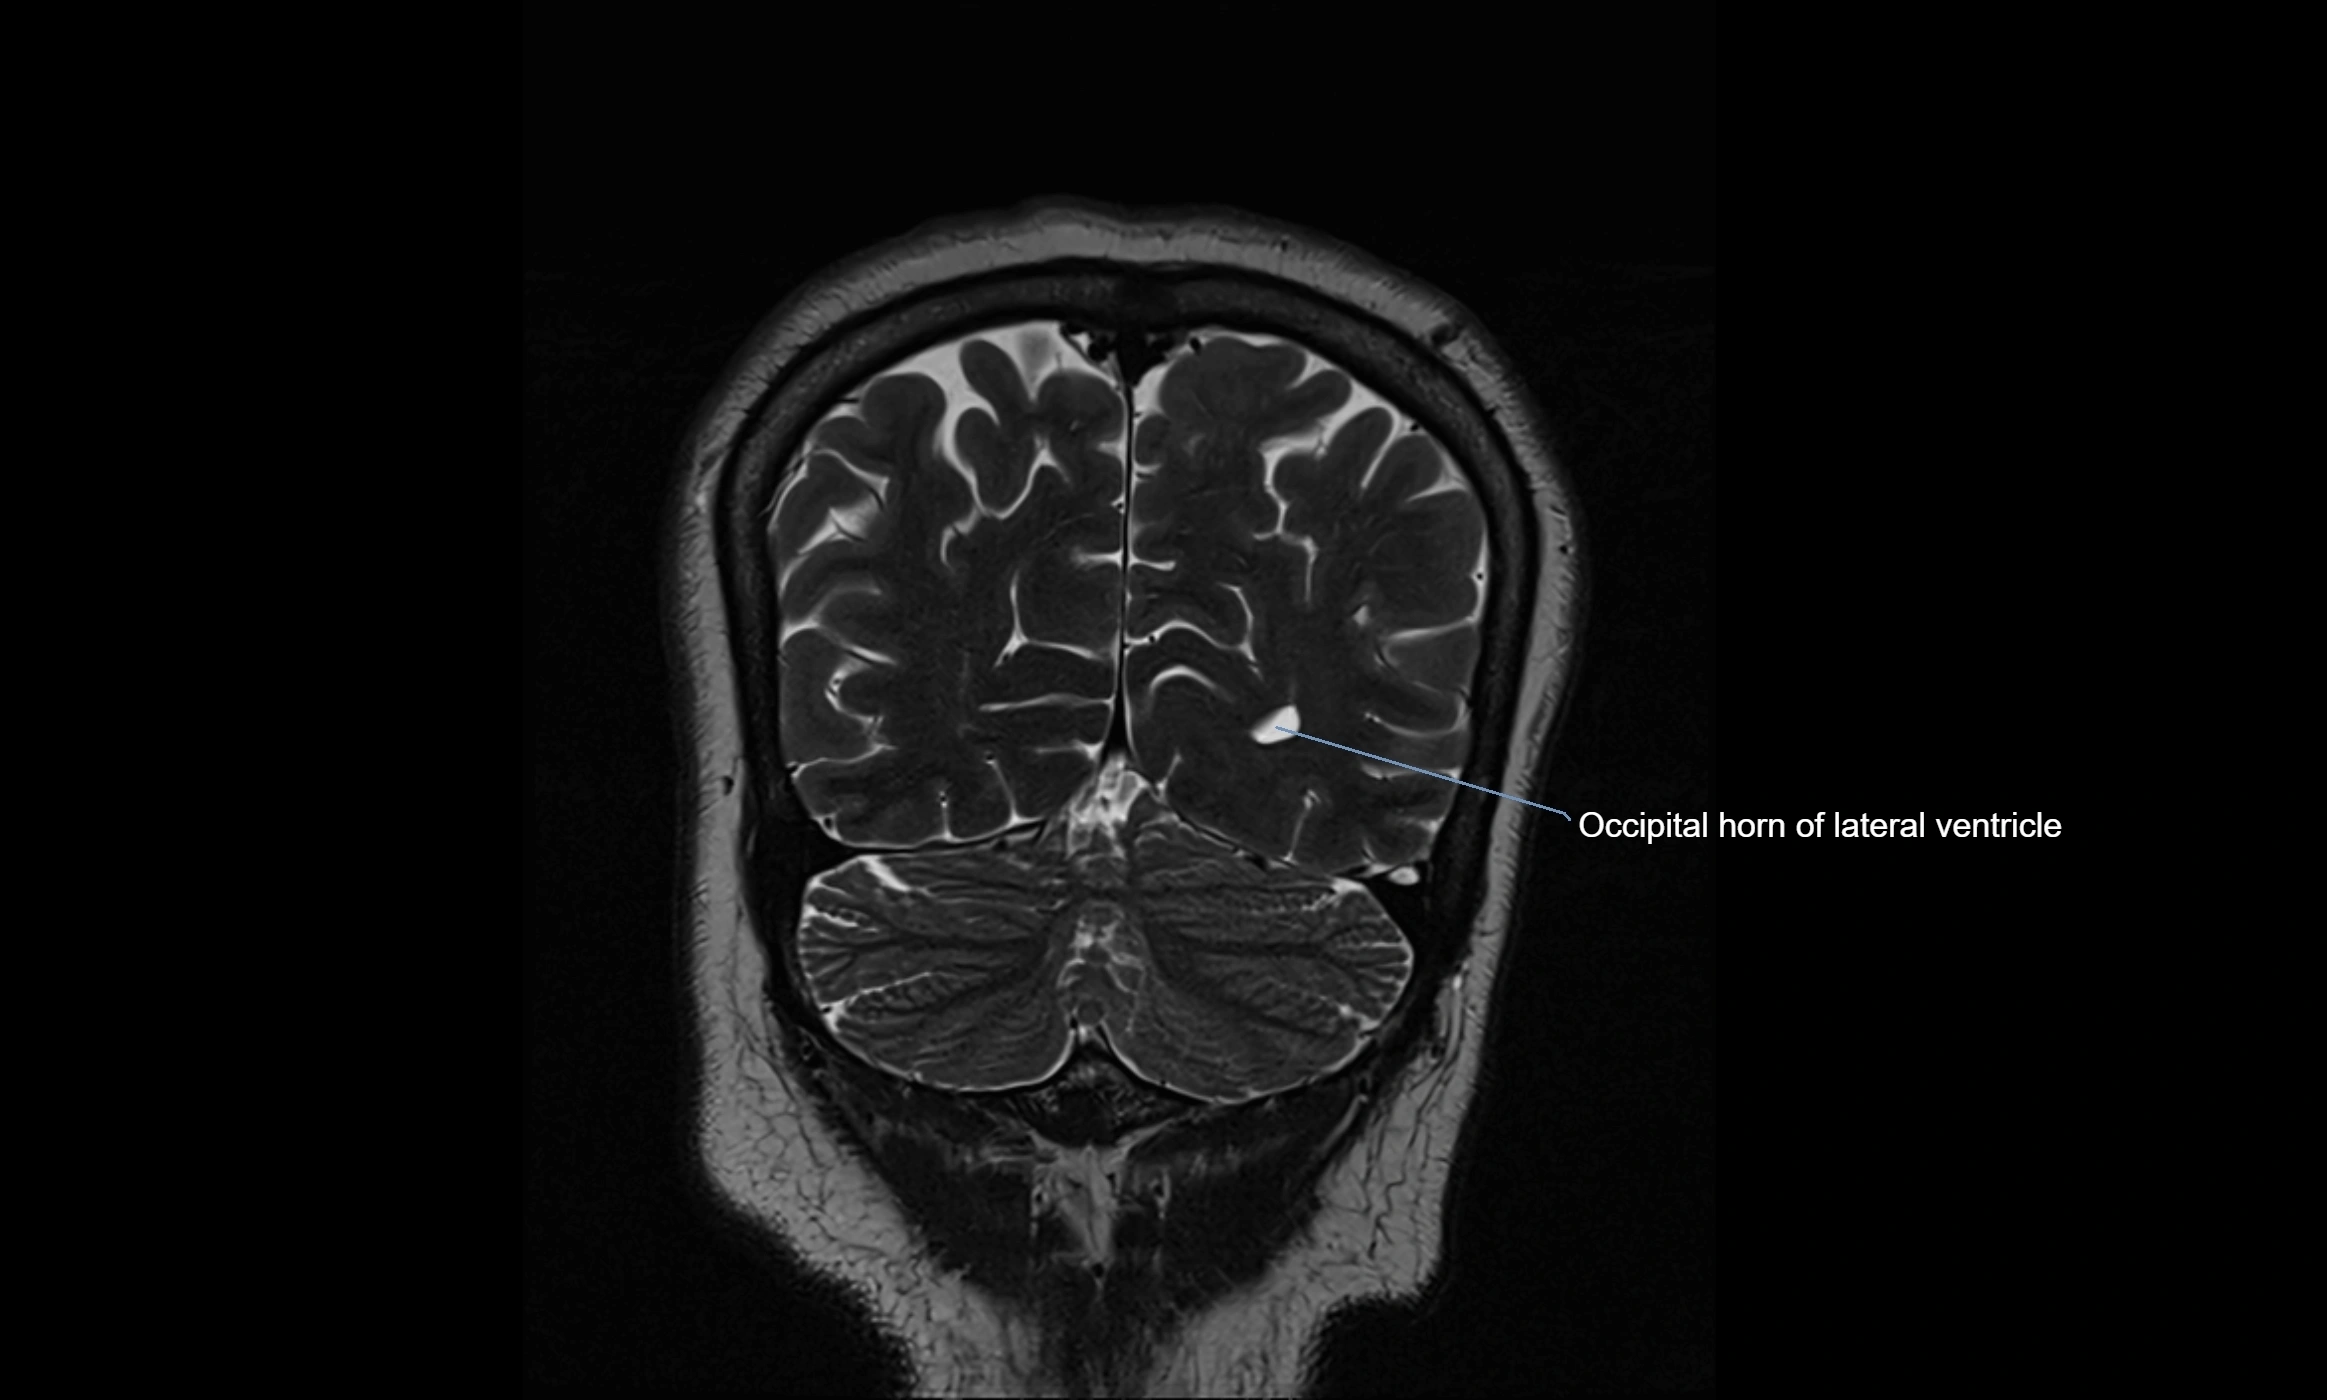

MRI images

image